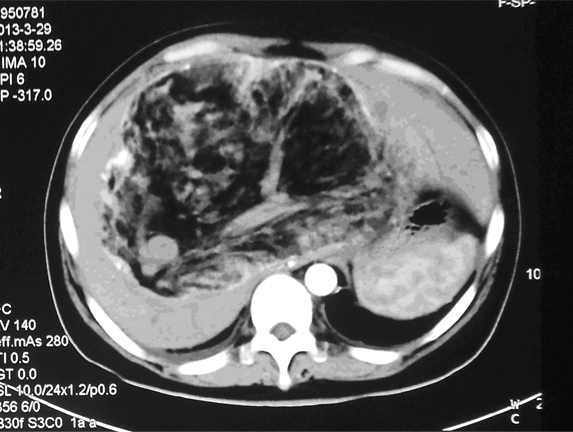

患者,女,31岁。于2013年3月4日查体发现肝脏肿物1月入院。无腹胀、腹痛、腹泻、发热等任何不适主诉。饮食正常,二便正常,体重无变化。查体:皮肤黏膜无黄染,无肝掌、蜘蛛痣。全身浅表淋巴结未触及。右肋部膨胀饱满,肝脏下缘位于右肋缘下约8 cm,剑突下5 cm,质地较软,边缘钝厚,表面无结节感,无压痛、触痛或叩痛。腹部移动性浊音(-);双下肢无水肿。辅助检查:上腹部CT示肝内巨大不均匀肿物,密度不均,内可见脂肪密度,不均匀强化,考虑肝脏巨大血管平滑肌脂肪瘤,见图 1。甲乙丙肝炎抗体均(-)。肝功能检查:正常;肿瘤标志物:AFP、CA199均在正常范围。2013年3月8日于我院行“剖腹探查术”:术中可见肝十二指肠韧带后方约20 cm×16 cm×16 cm巨大肿物,与肝门、肝左右叶、下腔静脉粘连,不能剥离,遂切除部分肿物送病理检查。术后病理结果:混合型脂肪肉瘤(上皮型与多形型之间过渡)。基于肿瘤巨大与周围组织粘连严重,无法手术切除,遂采取介入治疗,选择肝脏肿瘤供血动脉行灌注化疗及栓塞治疗。2013年4月9日第一次介入术中血管造影显示:肝动脉受压、移位、迂曲、增粗,实质期肝内可见巨块状肿瘤染色,由肝动脉及两侧膈动脉供血,肿瘤染色明显,肿瘤血管丰富交织呈网状,门静脉显影清晰,见图 2A、B。灌注化疗药物选择阿霉素、异环磷酰胺、达卡巴嗪;栓塞剂选择碘油、明胶海绵颗粒或海藻酸钠微球混合栓塞,术中患者均无不适。患者至2013年12月16日共行介入治疗6次,2014年1月20日复查CT示:肝脏肿瘤绝大部分液化、坏死,强化减轻,见图 3。血管造影示:肿瘤血管减少,血流量减少。随访:患者目前生存状态良好,无任何不适。

| Mass necrotic tumor tissue shown as soft tissue density 图3 肝脏原发性脂肪肉瘤患者介入治疗6次后的上腹部CT Figure 3 The upper abdominal CT image of the patient with primary liver liposarcoma after 6 times of interventional therapy |